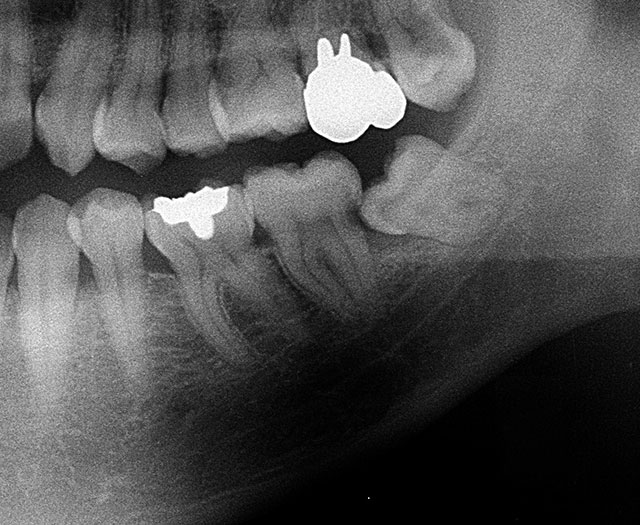

その決定的証拠写真がこれだ。

親知らずの生える方向が他の歯と同じように正しくて歯磨きによりしっかり清掃されればよいが、このレントゲンの患者では斜め前方向いて生え、歯冠の角が第2大臼歯の根元に食い込む形で止まっている。この場合第2大臼歯の後ろ側根元がむし歯になっている。

しかもこの場所は口の中をいくら念入りに見てもわからない。

レントゲンでしか見つからないのだ。冷たい水や甘い食べ物がしみると訴えて歯科医を訪れる患者が多いが、そのような状態の時は親知らずを抜いて、第2大臼歯の神経(歯髄)を取らなければならない。

レントゲンの患者は下顎の第2大臼歯がグラグラして痛いと訴えて来院した。

パノラマレントゲンで調べるとその歯1本だけその歯の周りの骨がなくなっている。

治療としては抜歯するしか仕方ない状況だった。

歯肉の内側に歯石も認められるので歯周病になっているのだが、抜歯しなくてはならないほど進行した決定的な原因は長期間1本の歯だけに強い力がかかっていたことだ。